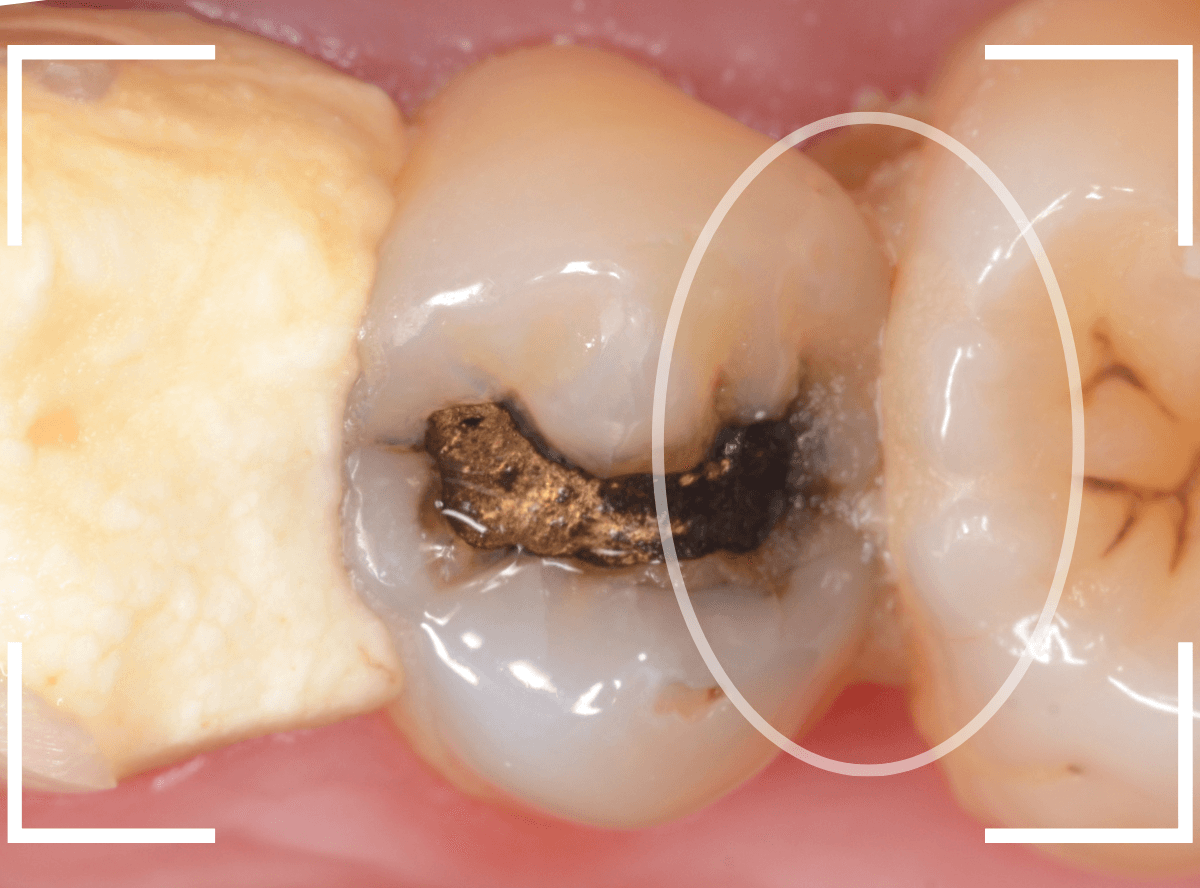

Case.24 レジンの下で虫歯が進行

上の奥歯の虫歯が見つかった患者さんです。

初診のチェックの際に、上から目視すると、レジンがつめてある〇部分が薄暗く黒くなっているので、これは虫歯があるな、とわかりました。

レントゲン写真で確認します。

赤いラインが虫歯と思われる部分、青いラインが歯の神経です。

先ほどの〇部分は明らかな虫歯になっているのがわかります。

この辺りはレジンがつめてありますが、その下もうっすらと虫歯になっていそうです。

治療を開始します。

先ほどの黒く見えた部分は少し削るとすぐに虫歯が出てきました。

手前の歯まで虫歯を除去した時点で、う蝕検知液で確認します。

赤く染色されている部分が虫歯です。

思ったよりも深めの虫歯ですね。

レジンを除去して虫歯をすべて治療したところです。

レジンの中も全体にうっすらと虫歯になっていました。

このくらいの虫歯でも、患者さんは自覚症状はありませんでした。

ご自身の自覚症状だけでは、虫歯の状況がわからないですし、自然に虫歯が治る事もありません。

いつものお話ですが、定期的なメンテナンスで、虫歯の早期発見・治療を心がけましょう。